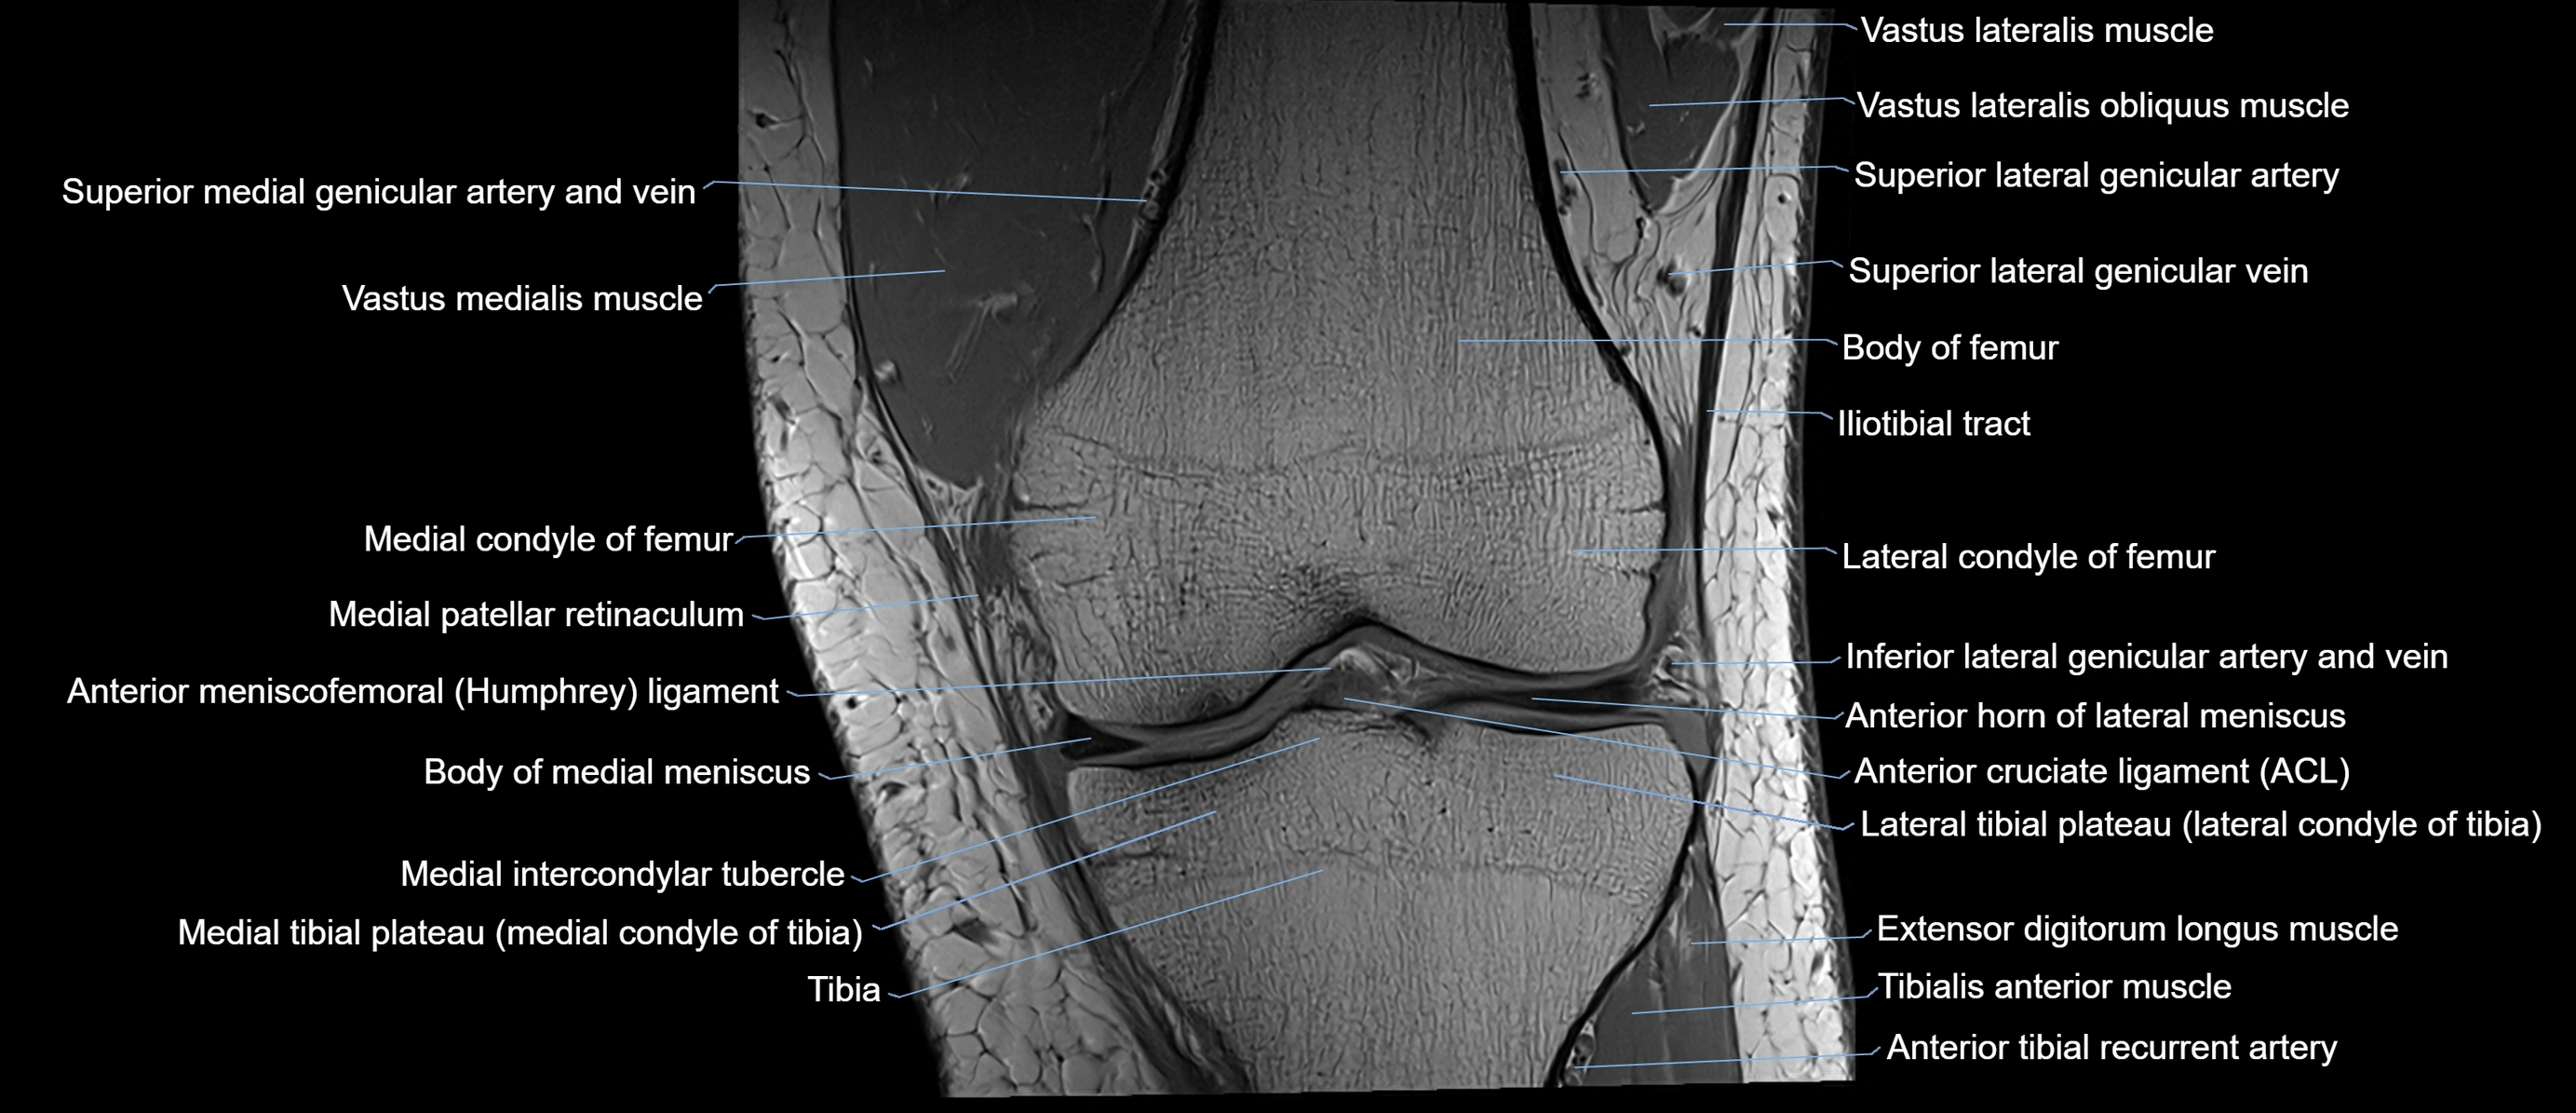

- Anterior cruciate ligament

- Anterior horn of lateral meniscus

- Anterior meniscofemoral ligament

- Body of lateral meniscus

- Body of medial meniscus

- Extensor digitorum longus muscle

- Inferior lateral genicular artery

- Inferior lateral genicular vein

- Lateral condyle of femur

- Lateral tibial plateau

- Medial condyle of femur

- Medial condyle of tibia

- Medial intercondylar tubercle

- Medial patellar retinaculum

- Medial tibial plateau

- Superior lateral genicular artery

- Superior lateral genicular vein

- Tibia

- Tibialis anterior muscle

- Vastus Lateralis Obliquus Muscle

- Vastus lateralis muscle

- Vastus medialis muscle

- great saphenous vein